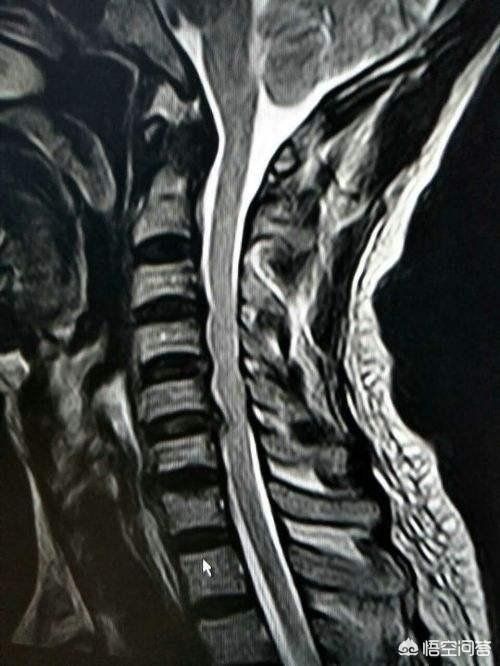

Wenn der Verdacht besteht, dass die Halswirbelsäule die Ursache der Schulterschmerzen ist, muss eine Untersuchung durchgeführt werdenMRT der HalswirbelsäuleIm Folgenden sind einige Beispiele aufgeführt, wie man sicherstellen kann, dass ein zervikaler Bandscheibenvorfall oder eine Anomalie in der knöchernen Struktur eine Nerveneinklemmung verursacht, und wenn dies mit einer Schwäche der Schultern oder der oberen Gliedmaßen einhergeht, kann es sogar notwendig sein, eineElektromyographieDie Untersuchung klärt, ob die Nerven geschädigt sind. BehandlungsmöglichkeitenAkupunktur und Moxibustion durchführen oder durchführen lassenNachfolgend sind einige der wichtigsten Fragen aufgeführt, die im Hinblick auf die Erreichung einer angemessenen(einen Wagen) ziehenWenn die Schmerzen stark sind, können SieOrale schmerzstillende und entzündungshemmende MedikamenteDa die meisten dieser Schmerzen auf ein Ödem an den Nervenwurzeln zurückzuführen sind, ist es möglich, einige oral einzunehmen.Medikamente gegen Ödeme,Sie können auch einige Physiotherapie wie transkutane elektrische Nervenstimulation, und in der Regel gibt es Erleichterung nach systematischer Behandlung. Diese Zeitspanne kann in der akuten Phase 1~2 Wochen dauern, und es wird etwa drei Monate dauern, bis sich die Beschwerden langsam bessern.Die Patienten müssen darauf vorbereitet sein und dürfen nichts überstürzen, denn bei dieser Art von Problemen muss man alles langsam angehen.。

Nachdem wir Schmerzen in der linken Schulter, die durch andere viszerale Erkrankungen verursacht werden, ausgeschlossen haben, müssen wir anhand der ersten Symptome des Patienten feststellen, ob es sich um eine Schultersteife oder eine Rotatorenmanschettenverletzung handelt. Denn die Anfangssymptome der Schultersteife und der Rotatorenmanschettenverletzung sind relativ ähnlich. Kürzlich lernte ich einen Patienten mit einer Rotatorenmanschettenverletzung kennen, bei dem in anderen Krankenhäusern eine Schultersteife diagnostiziert worden war, aber eines der Hauptsymptome des Patienten ließ nicht auf eine Schultersteife schließen. Es gab eindeutig mehrere ungünstige Aktivitäten in der Umgebung, sowohl aktive als auch passive Bewegungen waren eingeschränkt, wie z. B. die Unfähigkeit, die Schulter zu haken, die hintere Streckung und den hinteren Rücken, wie z. B. einige Bewegungen, Gurgeln, Kämmen der Haare und Berühren des Rückens. Bei der Verletzung der Rotatorenmanschette handelt es sich hauptsächlich um einen Riss der Supraspinatussehne, die Supraspinatussehne ist hauptsächlich unfähig, die Schulter zu heben, und auf dem MRT ist deutlich zu sehen, dass die Supraspinatussehne am Übergang zum Oberarmknochen deutlich ödematös oder sogar gerissen ist.

Hier ist es wichtig, zwischen Schulterschmerzen und Schmerzen in der Schulterregion zu unterscheiden. Auf dieser Seite der linken Schulter befindet sich das Herz, und wenn eine akute Ischämie des Herzens oder eine Angina pectoris bei einer koronaren Herzkrankheit vorliegt, strahlt diese nach oben aus und verursacht Symptome wie Schulterschmerzen, was etwas anderes ist. Selbst wenn der Schmerz die lokale Bewegung nicht beeinträchtigt und man den Schmerz in diesem Bereich nicht spürt, aber nicht weiß, wo er ist, steht der Schmerz wahrscheinlich mit dem Herzen in Verbindung, so dass er manchmal in den Rücken oder die Brust ausstrahlt, und in manchen Fällen muss man zur Untersuchung des Herzens ins Krankenhaus gehen. Wenn auszuschließen, weil das Herz durch die Situation verursacht, nur Schulterschmerzen, ist es anders, zu fragen, der Patient hat keine Geschichte von Trauma, wie alt, etc., bis zum Alter von 50 Jahren oder so, vielleicht ist es eine Krankheit namens frozen shoulder oder frozen shoulder, Schmerzen plus eingeschränkte Aktivität, dann an diesem Punkt, wenn die Diagnose der innerhalb der Abwesenheit von speziellen Verletzungen, oder Physiotherapie, Medikamente, funktionelle Übung. Wenn sich bei der Untersuchung herausstellt, dass der Patient eine schlechte Beweglichkeit und eine Vorgeschichte von Traumata hat oder älter ist, ist es am sichersten, eine ärztliche Untersuchung durch einen Arzt durchführen zu lassen, zusammen mit bildgebenden Untersuchungen, wie z. B. einer MRT, um zu prüfen, ob wichtige Sehnen und Bänder im Zusammenhang mit dem Schultergelenk verletzt sind, einschließlich Verletzungen der Rotatorenmanschette, Risse der Glenoidlippe und so weiter. Wenn es Probleme mit der inneren Struktur gibt, ist oft eine chirurgische Behandlung erforderlich. Derzeit sind die chirurgischen Methoden bereits sehr wissenschaftlich, und die meisten von ihnen sind minimalinvasive Operationen, d.h. die so genannte Schulterarthroskopie, bei der zwei oder drei Löcher gemacht werden, um die Stelle zu finden und sie auf minimalinvasive Weise zu reparieren und zu rekonstruieren, um die Krankheit zu heilen.